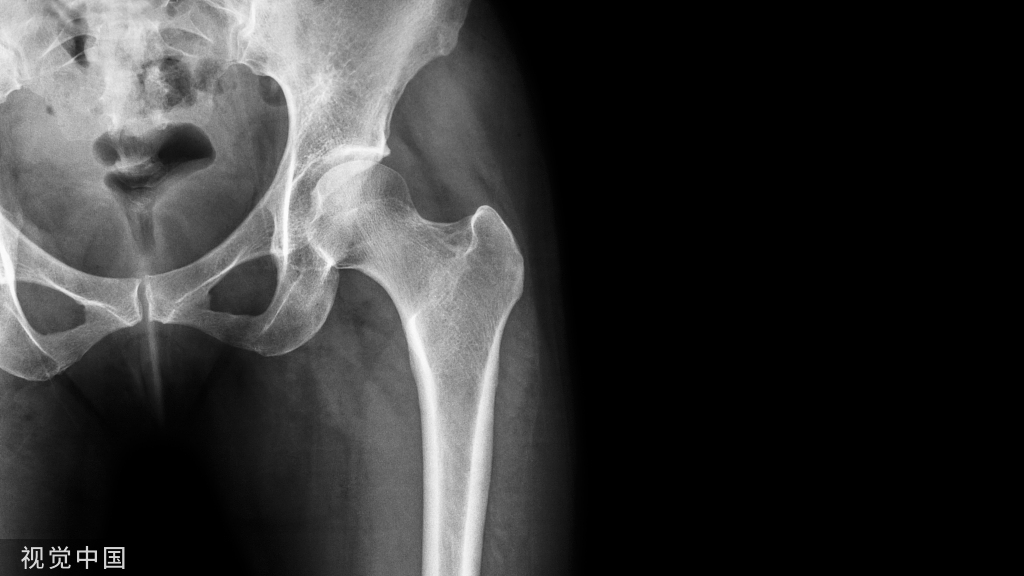

3.远端断钉,比较少见

远端的锁定断裂可能是在远端动力加压时的问题

远端锁定不居中也会引起该问题

髓腔过于宽大的患者,骨折复位不良,头钉固定较好,整体出现应力集中在远端